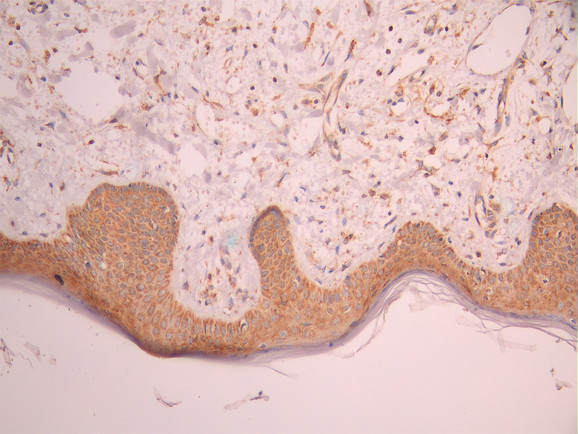

IHC image of CSB-RA272247A0HU diluted at 1:100 and staining in paraffin-embedded human skin tissue performed on a Leica BondTM system. After dewaxing and hydration, antigen retrieval was mediated by high pressure in a citrate buffer (pH 6.0). Section was blocked with 10% normal goat serum 30min at RT. Then primary antibody (1% BSA) was incubated at 4°C overnight. The primary is detected by a Goat anti-rabbit polymer IgG labeled by HRP and visualized using 0.05% DAB.